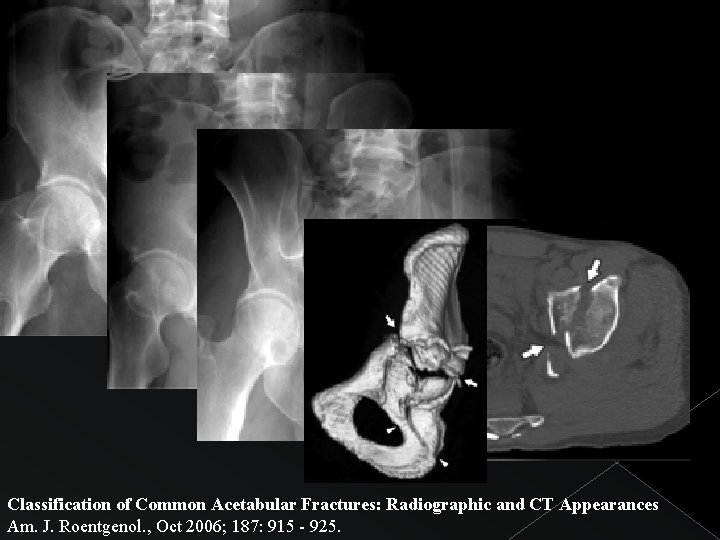

FRACTURA DE AMBAS COLUMNAS Afectación de: Columna anterior + Columna posterior Línea iliopectinea Línea ilioisquiática Extensión hacia: Anillo obturador + Pala ilíaca Signo patognomónico: “Spur sign” (“signo de la espuela”): desplazamiento posterior de sciatic butress desconexión del techo acetabular con el esqueleto axial. Radiograficamente: fragmento óseo que se extiende posteriormente a nivel superior acetabular.

Classification of Common Acetabular Fractures: Radiographic and CT Appearances Am. J. Roentgenol. , Oct 2006; 187: 915 - 925.